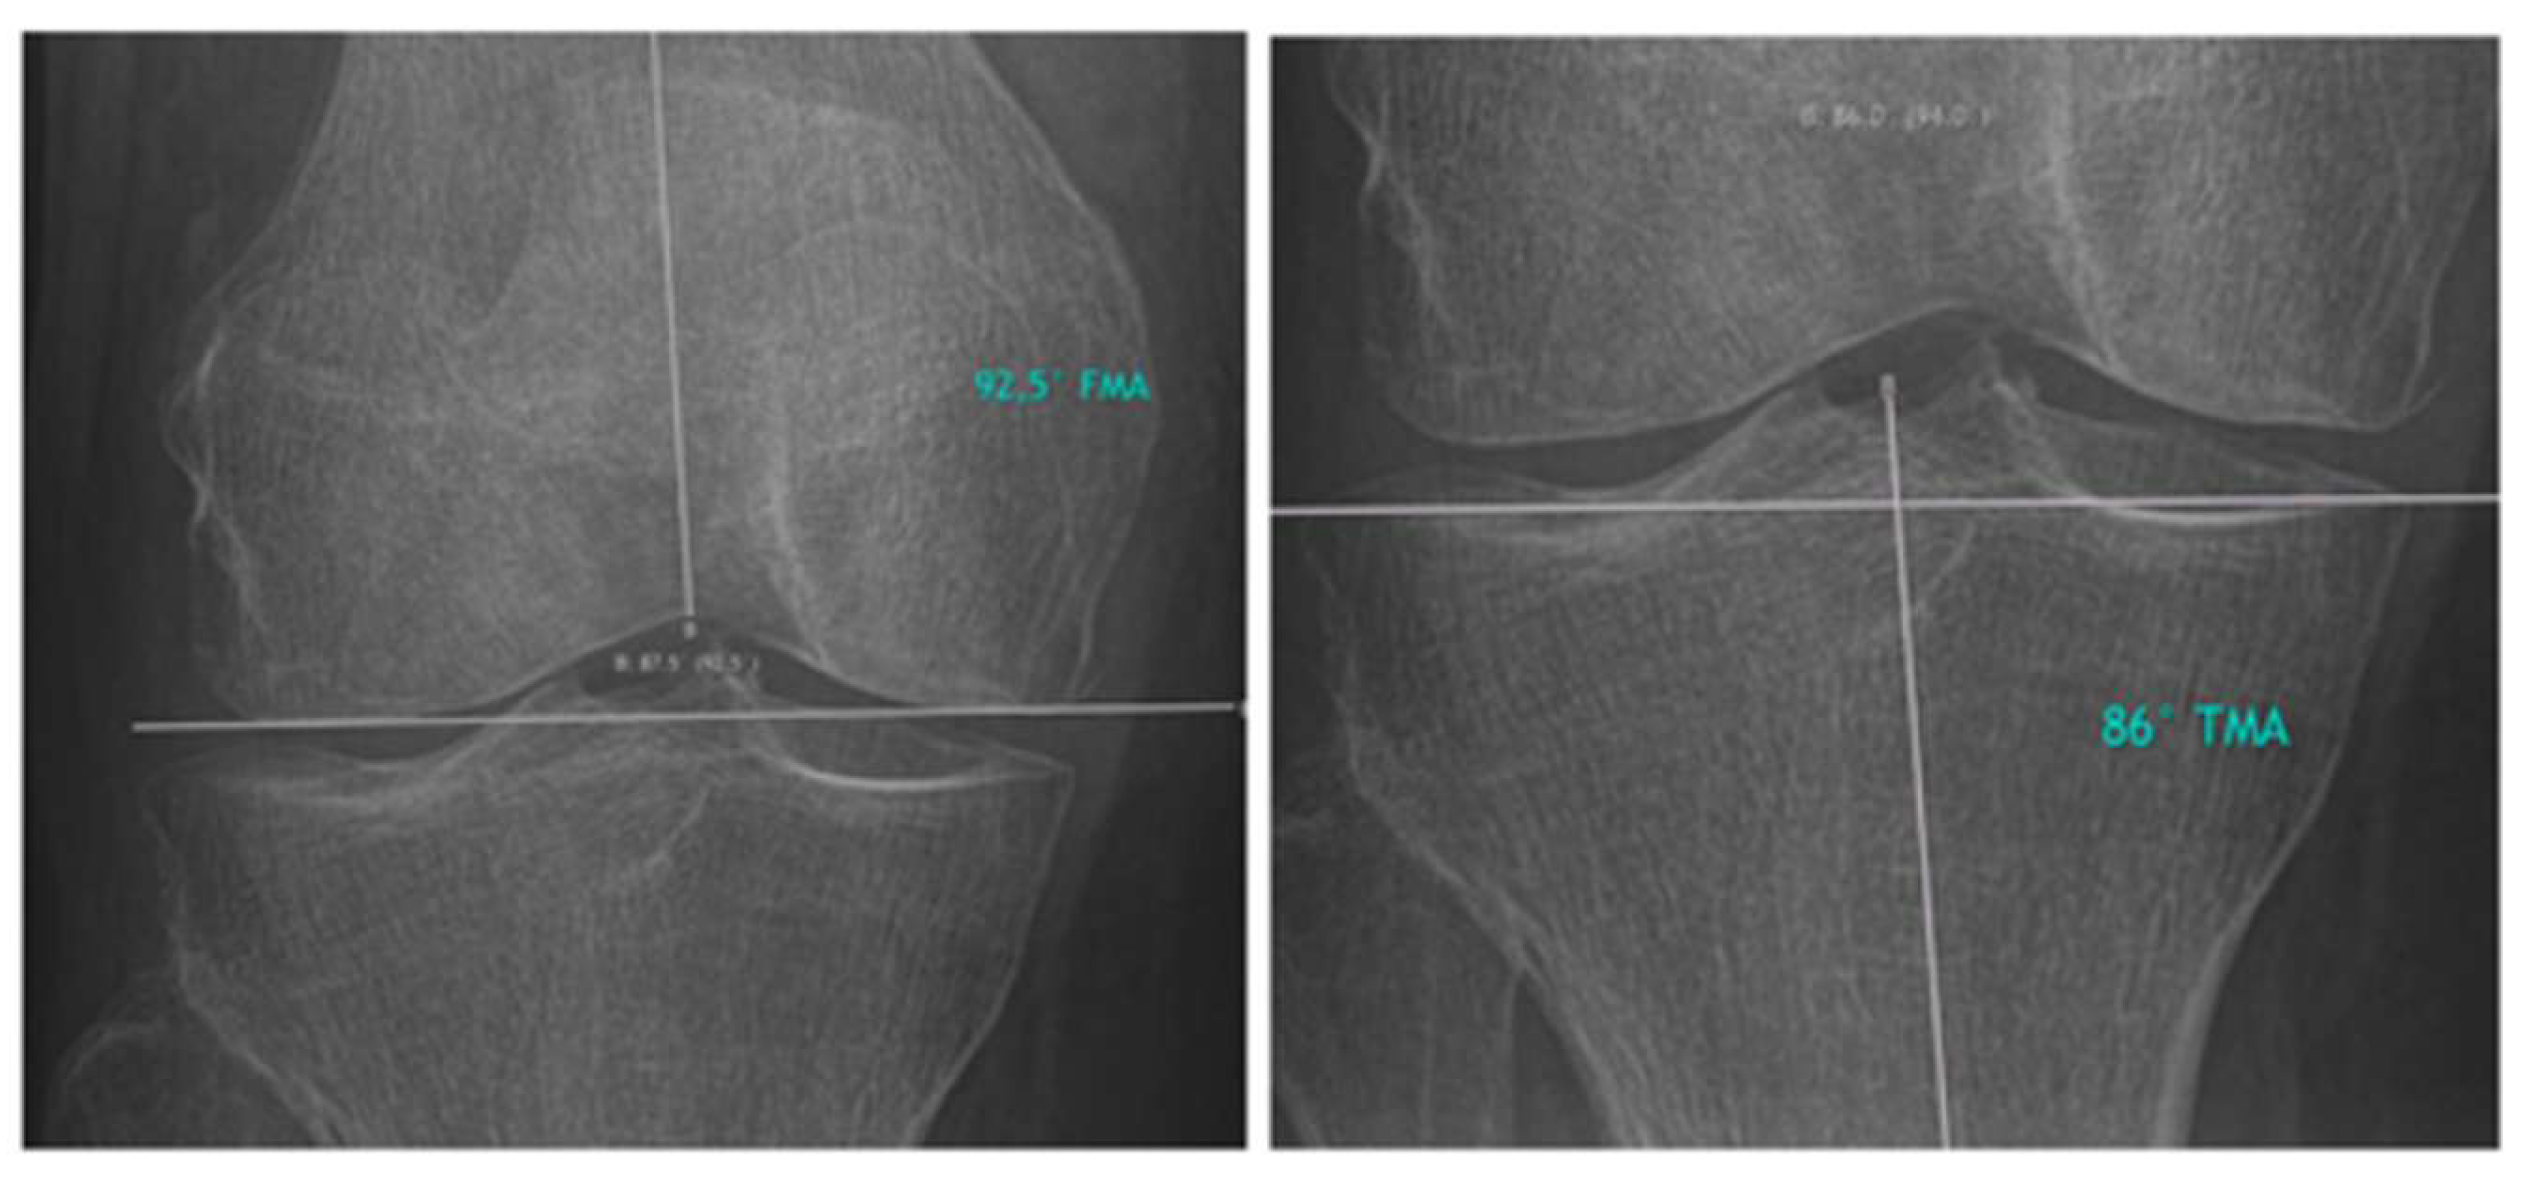

Hirschmann et al. introduced a novel classification for phenotyping coronal lower limb alignment [15,16,17,18,19]. The measurement techniques described by Hirschmann et al. for assessing the femoral mechanical angle (FMA) and the tibial mechanical angle (TMA) were applied in this study. The measurements are presented in Figure 2.

Figure 2. FMA and TMA measurements were performed on the THA side pre- and postoperatively.